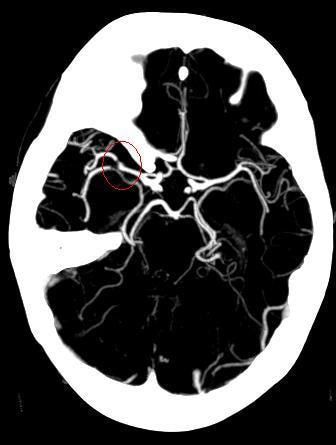

Ischemic stroke is characterized by the sudden loss of blood circulation to an area of the brain, resulting in a corresponding loss of neurologic function. Acute ischemic stroke is caused by thrombotic or embolic occlusion of a cerebral artery and is more common than hemorrhagic stroke.The International Classification of Diseases, 10th Revision, Clinical Modification (ICD-10-CM) code for “cerebral infarction” is I63. It includes occlusion and stenosis of cerebral and precerebral arteries, resulting in cerebral infarction.Consider stroke in any patient presenting with acute neurologic deficit or any alteration in level of consciousness. Common stroke signs and symptoms include the following: Abrupt onset of hemiparesis, monoparesis, or (rarely) quadriparesis Hemisensory deficits Monocular or binocular visual loss Visual field deficits Diplopia Dysarthria Facial droop Ataxia Vertigo (rarely in isolation) Nystagmus Aphasia Sudden decrease in level of consciousness Emergent brain imaging is essential for evaluation of acute ischemic stroke. Non-contrast computed tomography (CT) scanning is the most commonly used form of neuroimaging in the acute evaluation of patients with apparent acute stroke. A lumbar puncture is required to rule out meningitis or subarachnoid hemorrhage when the CT scan is negative but the clinical suspicion remains high.